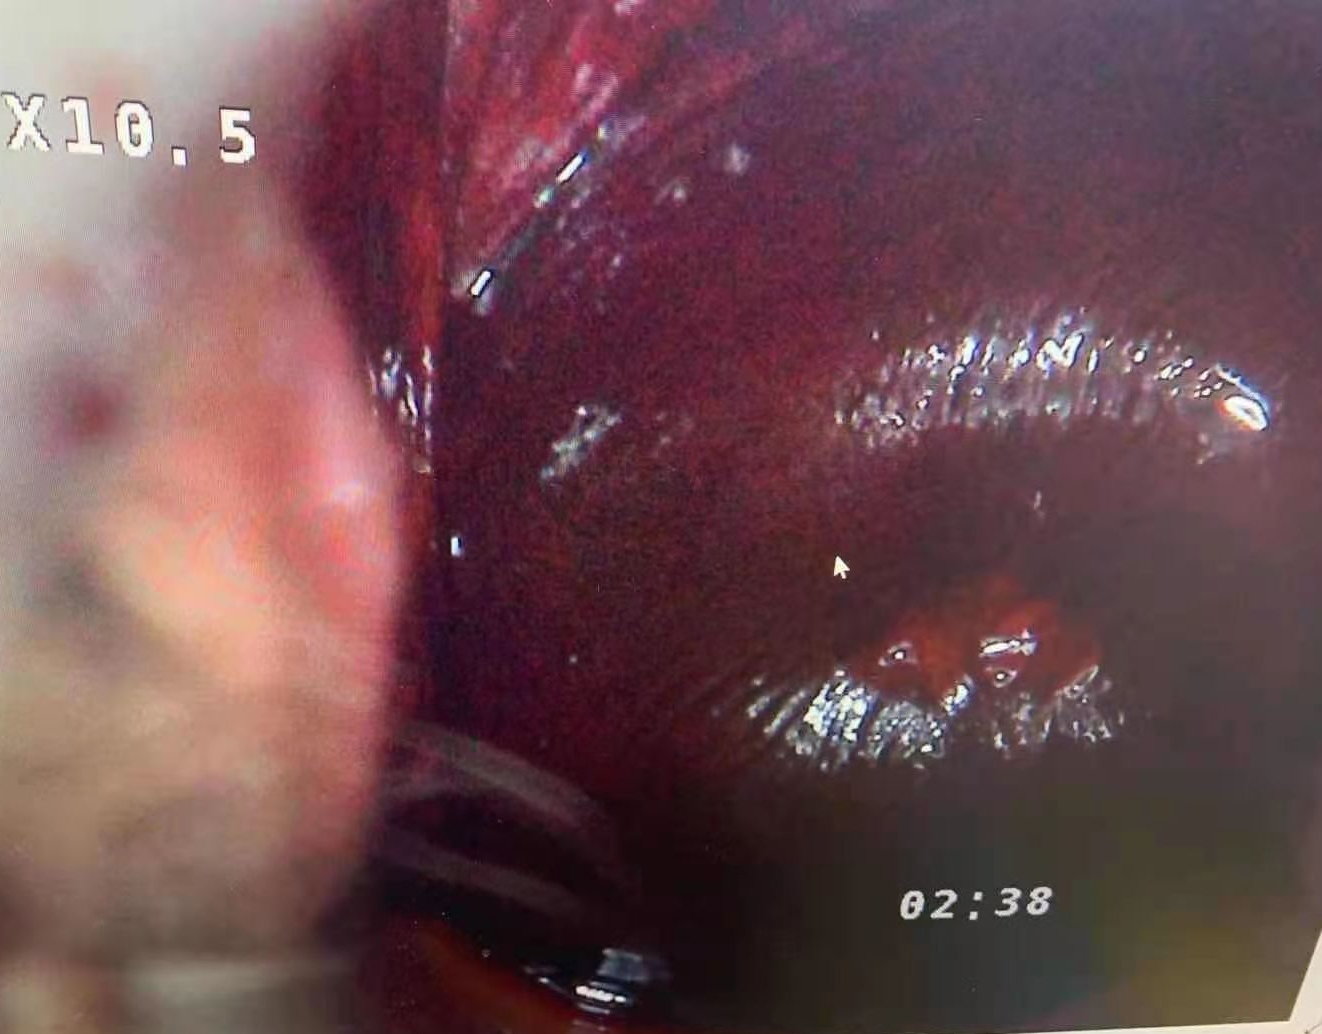

**Extra long depth of field, super large field of view, super three-dimensional sense, realistic color reproduction, unique light path design, providing true 3D visual effects for pre-cancerous, pre-lesional punctiform vessels, columnar epithelium and some tiny lesions .

**50times System Magnification ,17 times optical amplication,3 times Digital amplification.able to output divine clear view of the examination lesion parts. Provide doctors with 3D visual image of the epithelial tissues,and different levels of the blood vessels. **LED light source,lifespan more than 20,000hours. **Horizontal Resolution up to 2064.

Real cervical diagnosis pictures